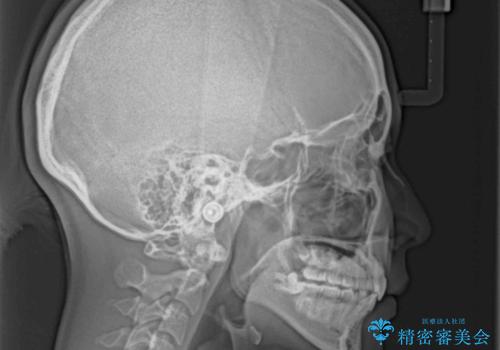

指が入るくらいに隙間のある上下前歯 抜歯矯正で横顔の印象が大きく改善

高校生ということもあり、治療期間は2年を切るスピードでした。

舌の突出癖は十分に改善されたとは言えない状態でしたので、今後の後戻り防止対策として、経過観察中も舌のトレーニング指導を行っていくこととなります。